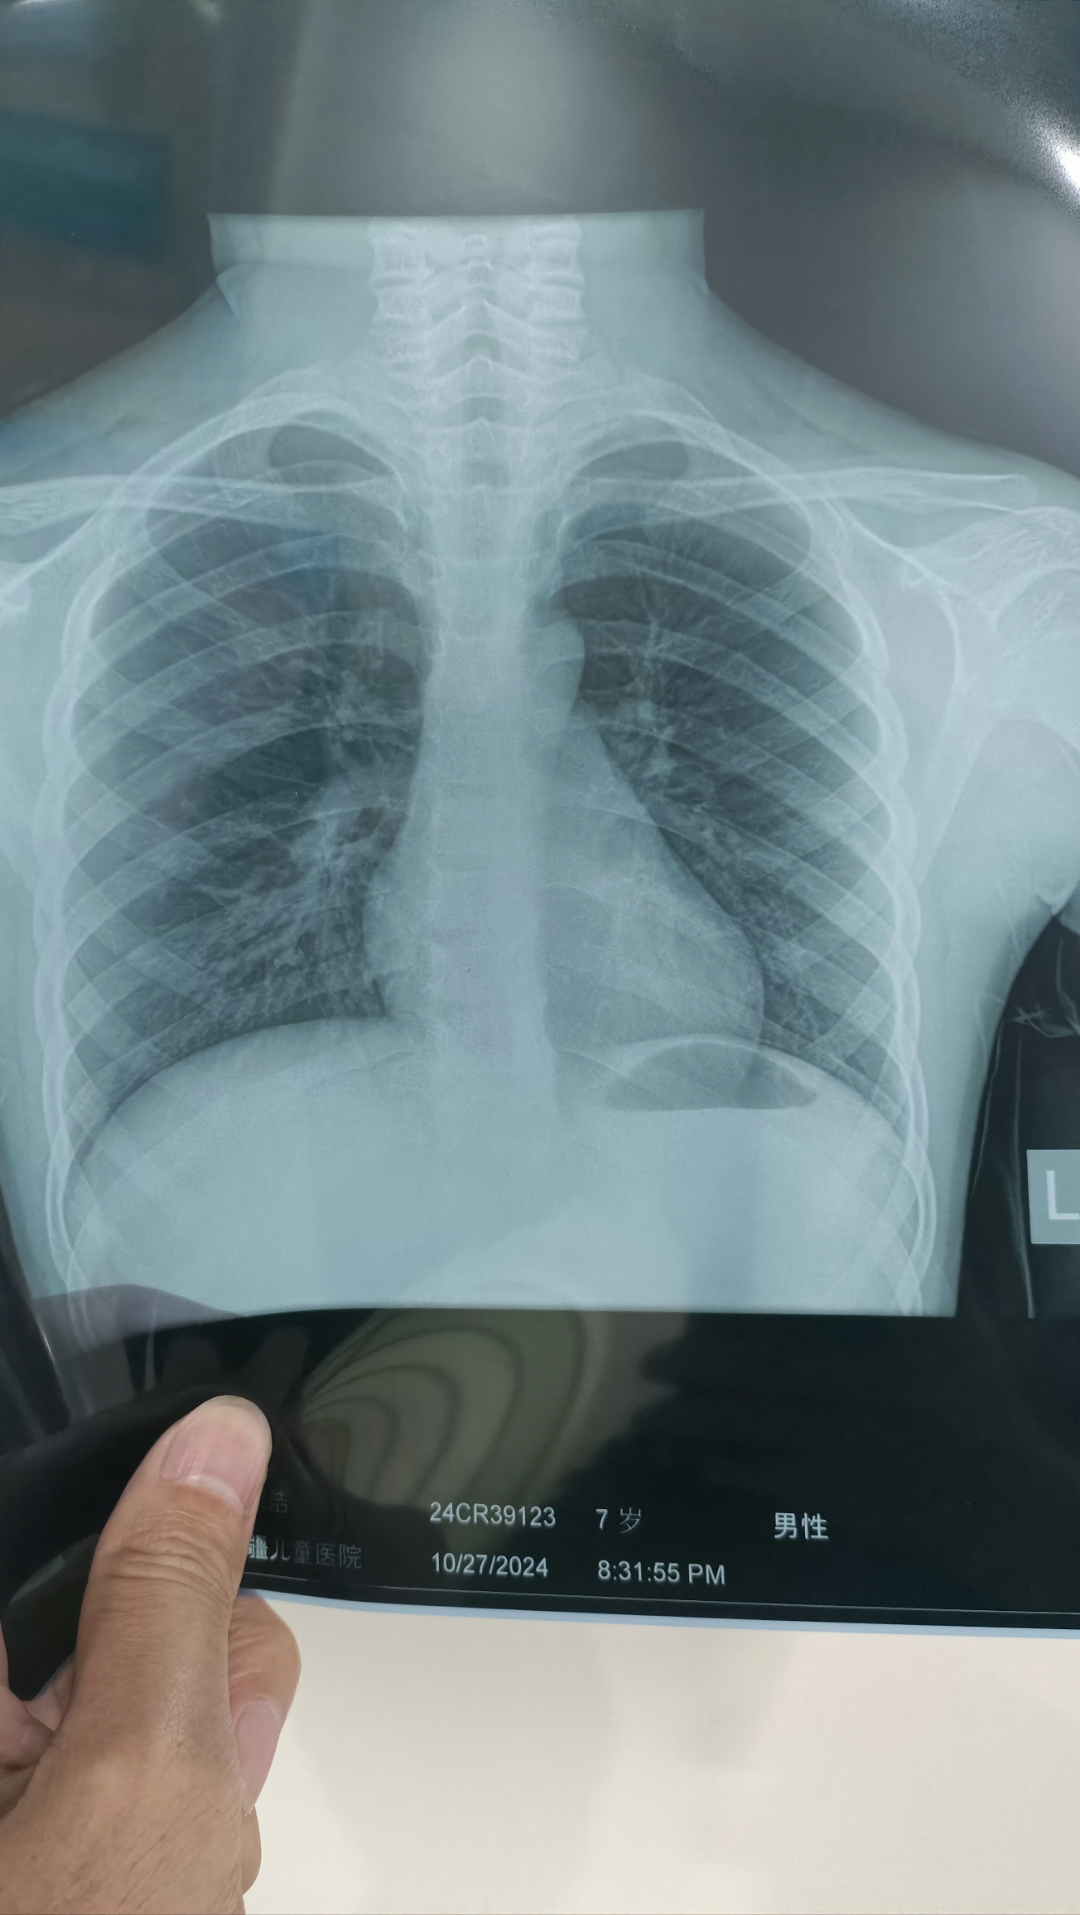

大神们看看,有肺炎么?

论肺ct的重要性,最近大叶性肺炎,重症肺炎多见,下图胸片对比右侧相对

图1这个小姑娘4岁,咳嗽发热5天, x光片发现右侧大叶性肺炎